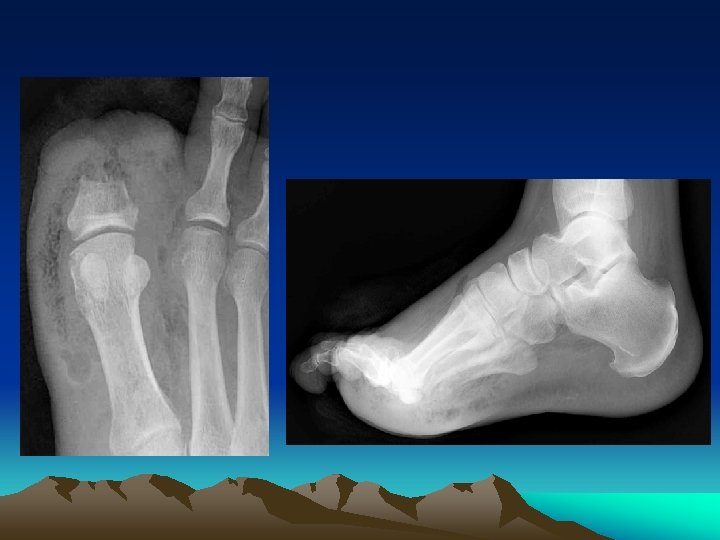

Diagnosis • Must be distinguished from gas gangrene, pyomyositis, and myositis. • Blood tests typically demonstrate a leukocytosis with a marked left shift, and elevations in the serum creatine kinase and creatinine concentrations. • Imaging - Soft tissue x-rays, CT scan and MRI